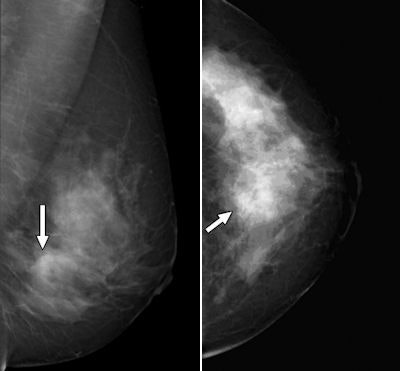

| Left, 48-year-old woman with palpable lesion in right upper breast found by her physician. Focal sonogram at site of palpable mass at 12-o'clock position shows highly suspicious irregular hypoechoic 1.4-cm mass (calipers) in posterior breast. Right, 48-year-old woman with palpable lesion in right upper breast found by her physician. Sagittal contrast-enhanced T1-weighted MR image with fat saturation shows index cancer (long arrow). Second cancer (short arrow) detected on MRI only is seen in inferior breast, 5.5 cm from incident cancer. Subsequent core biopsy confirmed that second area was another focus of grade I invasive ductal carcinoma. Fig 1c, d. Godinez J, Gombos EC, Chikarmane SA, Griffin GK, Birdwell RL. AJR. 2008;191(1):272-277. |